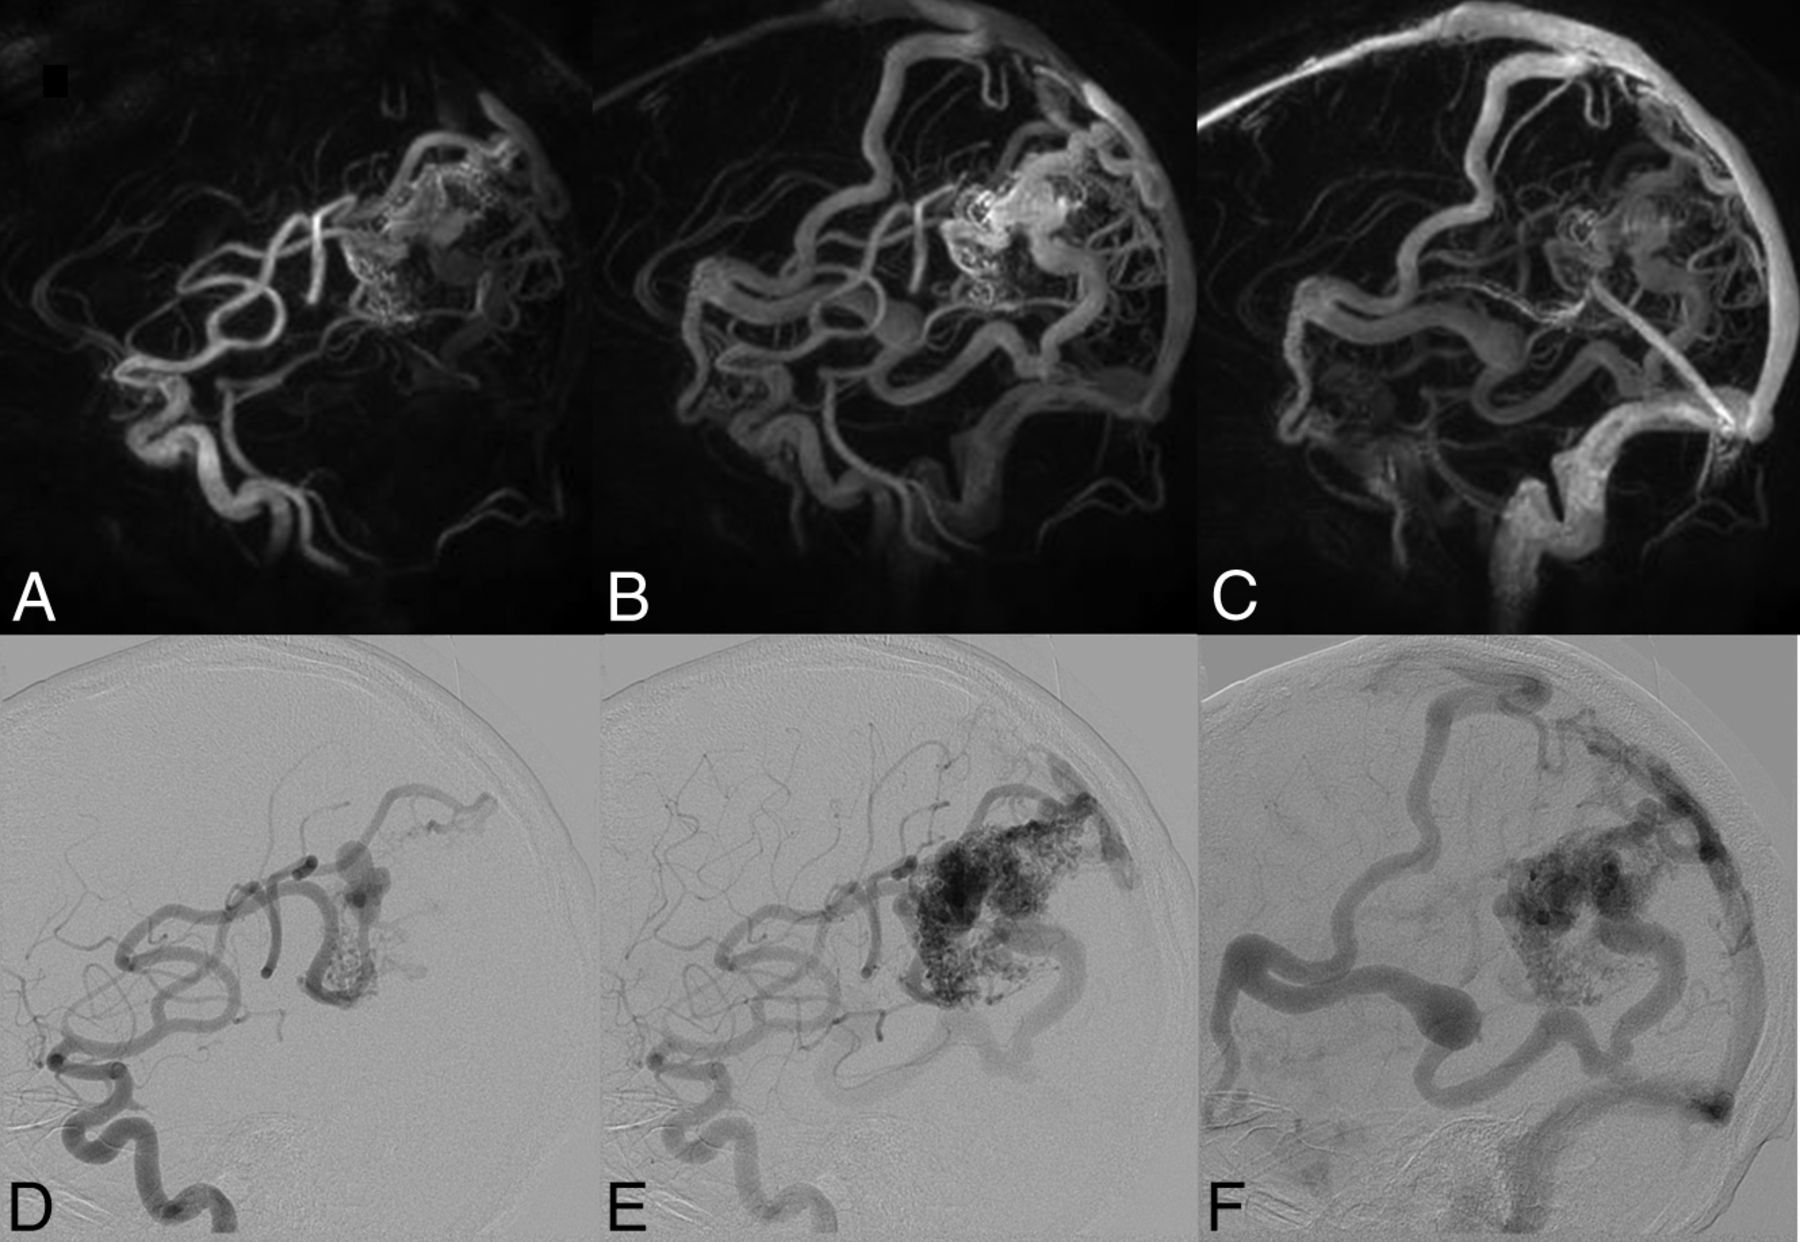

When we compared M2/M3 arterial branches, there was no significant difference between the mean image quality scores of HYPRFlow (3.18) and TOF (3.26) (P > .05), but there were very significant differences between the image quality of both HYPRFlow and TOF compared with DSA (3.94) with P < .002 and .004, respectively. DSA deep and superficial venous image quality (3.82) was significantly better than HYPRFlow (3.08) (P < .005) (Figs 2⇓–4).

Right temporal lobe AVM. Top row: 3 HYPRFlow images from the 60-image dynamic series. Arterial (A), mixed (B), and venous phase (C) images are displayed. Bottom row: corresponding DSA arterial (D), mixed (E), and venous phase (F) images. The HYPRFlow images demonstrate the cortical venous drainage similar to the DSA.